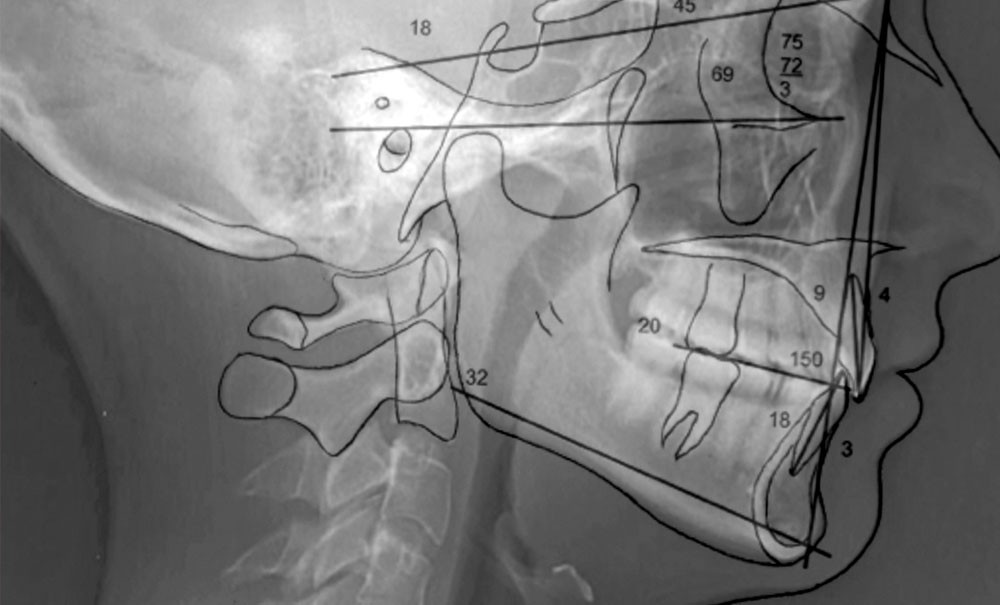

La radiographie panoramique et la téléradiographie de profil objectivent (fig. 3 et 4) :

- un espace rétro-molaire suffisant pour une distalisation ;

- des axes radiculaires molaires favorables à un redressement ;

- une classe I squelettique (angle ANB = 3°) ;

- une normodivergence (angle GoGn/SN = 32°)…